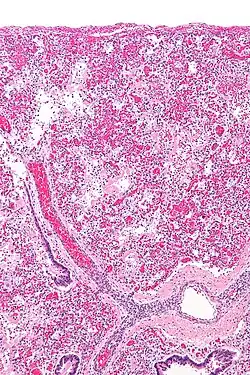

Micrograph of diffuse alveolar damage, the histologic correlate of ARDS. H&E stain.

ARDS is a form of fluid accumulation in the lungs not explained by heart failure (noncardiogenic pulmonary edema). It is typically provoked by an acute injury to the lungs that results in flooding of the lungs' microscopic air sacs responsible for the exchange of gases such as oxygen and carbon dioxide with capillaries in the lungs.[13] Additional common findings in ARDS include partial collapse of the alveoli (atelectasis) and low levels of oxygen in the blood (hypoxemia). The clinical syndrome is associated with pathological findings including pneumonia, eosinophilic pneumonia, cryptogenic organizing pneumonia, acute fibrinous organizing pneumonia, and diffuse alveolar damage (DAD). Of these, the pathology most commonly associated with ARDS is DAD, which is characterized by a diffuse inflammation of lung tissue. The triggering insult to the tissue usually results in an initial release of chemical signals and other inflammatory mediators secreted by local epithelial and endothelial cells.

Neutrophils and some T-lymphocytes quickly migrate into the inflamed lung tissue and contribute in the amplification of the phenomenon. The typical histological presentation involves diffuse alveolar damage and hyaline membrane formation in alveolar walls. Although the triggering mechanisms are not completely understood, recent research has examined the role of inflammation and mechanical stress.